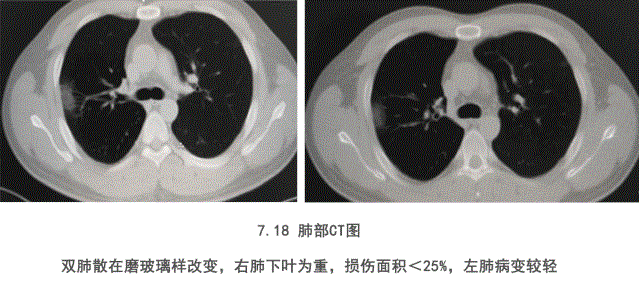

35岁的王先生(化名),是国内某知名企业的驻外员工,此次公派到非洲肯尼亚负责解决当地技术问题。但没想到却中招新冠病毒,感染入院。在病情恶化无计可施的情况下,中方医生提出给予特异性免疫球蛋白进行治疗的建议。在经过3天的治疗后,患者各项临床指标都呈好转趋势,最终王先生康复出院。主治医生也在对新冠特异免疫球蛋白治疗新冠肺炎进行总结时表示,新冠特异性免球蛋白对重症新冠肺炎治疗有效。控制炎症,迅速改善症状,恢复体力效果显著。